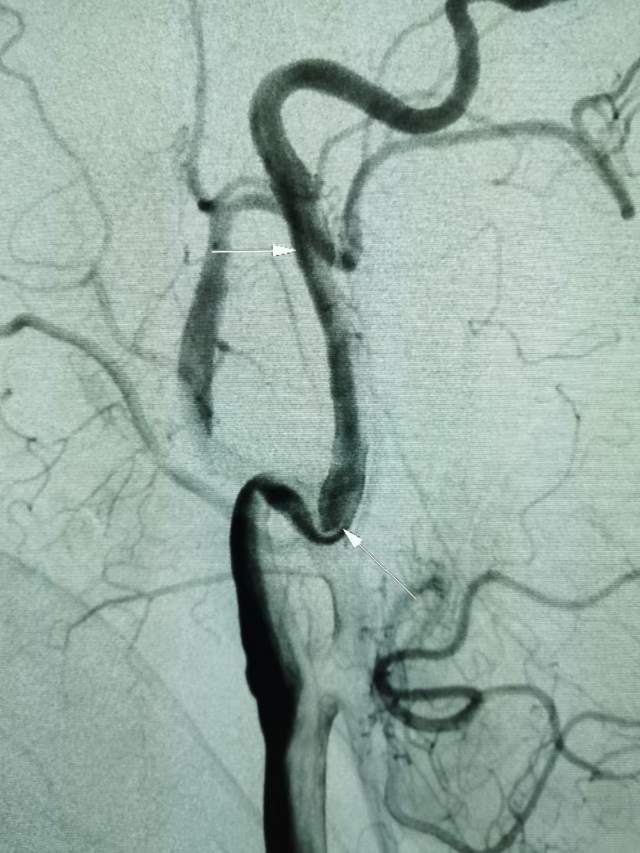

46岁青年女性患者,无高血压和糖尿病病史,突发大面积脑梗塞(图1-2)

遗留右侧肢体残疾,尽管卧床康复3个月,肢体也只能在床上平移,无法抬离床面,完全性失语,不能说话。家属老爸经人介绍辗转收入我科,看看能否得到进一步的改善。第一次晨间病房查房,看到纯朴、善良、苍老的老爸站在床边,向我们不紧不慢的诉说着女儿的病情,年轻秀丽的女儿静静躺在床上,一言不发(完全性失语),想到独生子女家庭在老年突然遭遇失独、残疾等意外后,本是年轻人照顾老年人的季节,现如今却成了白发人弓着背照顾残疾的黑发人,让人心中一阵苍凉和心酸。患者左侧大面积脑梗塞三个月,右侧肢体肌力只有2级,完全性失语;左侧大脑前动脉向左侧大脑中动脉代偿供血,基于上述情况,可能能够做的外科工作并不多,进一步康复的希望也不大。尽管如此,我们还是认真的对患者进行了详尽细致的评估,看看能否找到突破点。造影发现患者颈内动脉起始部存在颈动脉蹼(可能是三个月前引起梗塞的原因,图3)

还有两处隐约可见的颈动脉夹层,造影期间血管局部构型短时间内出现改变,提示夹层影响远端血流,修复夹层对患者至关重要